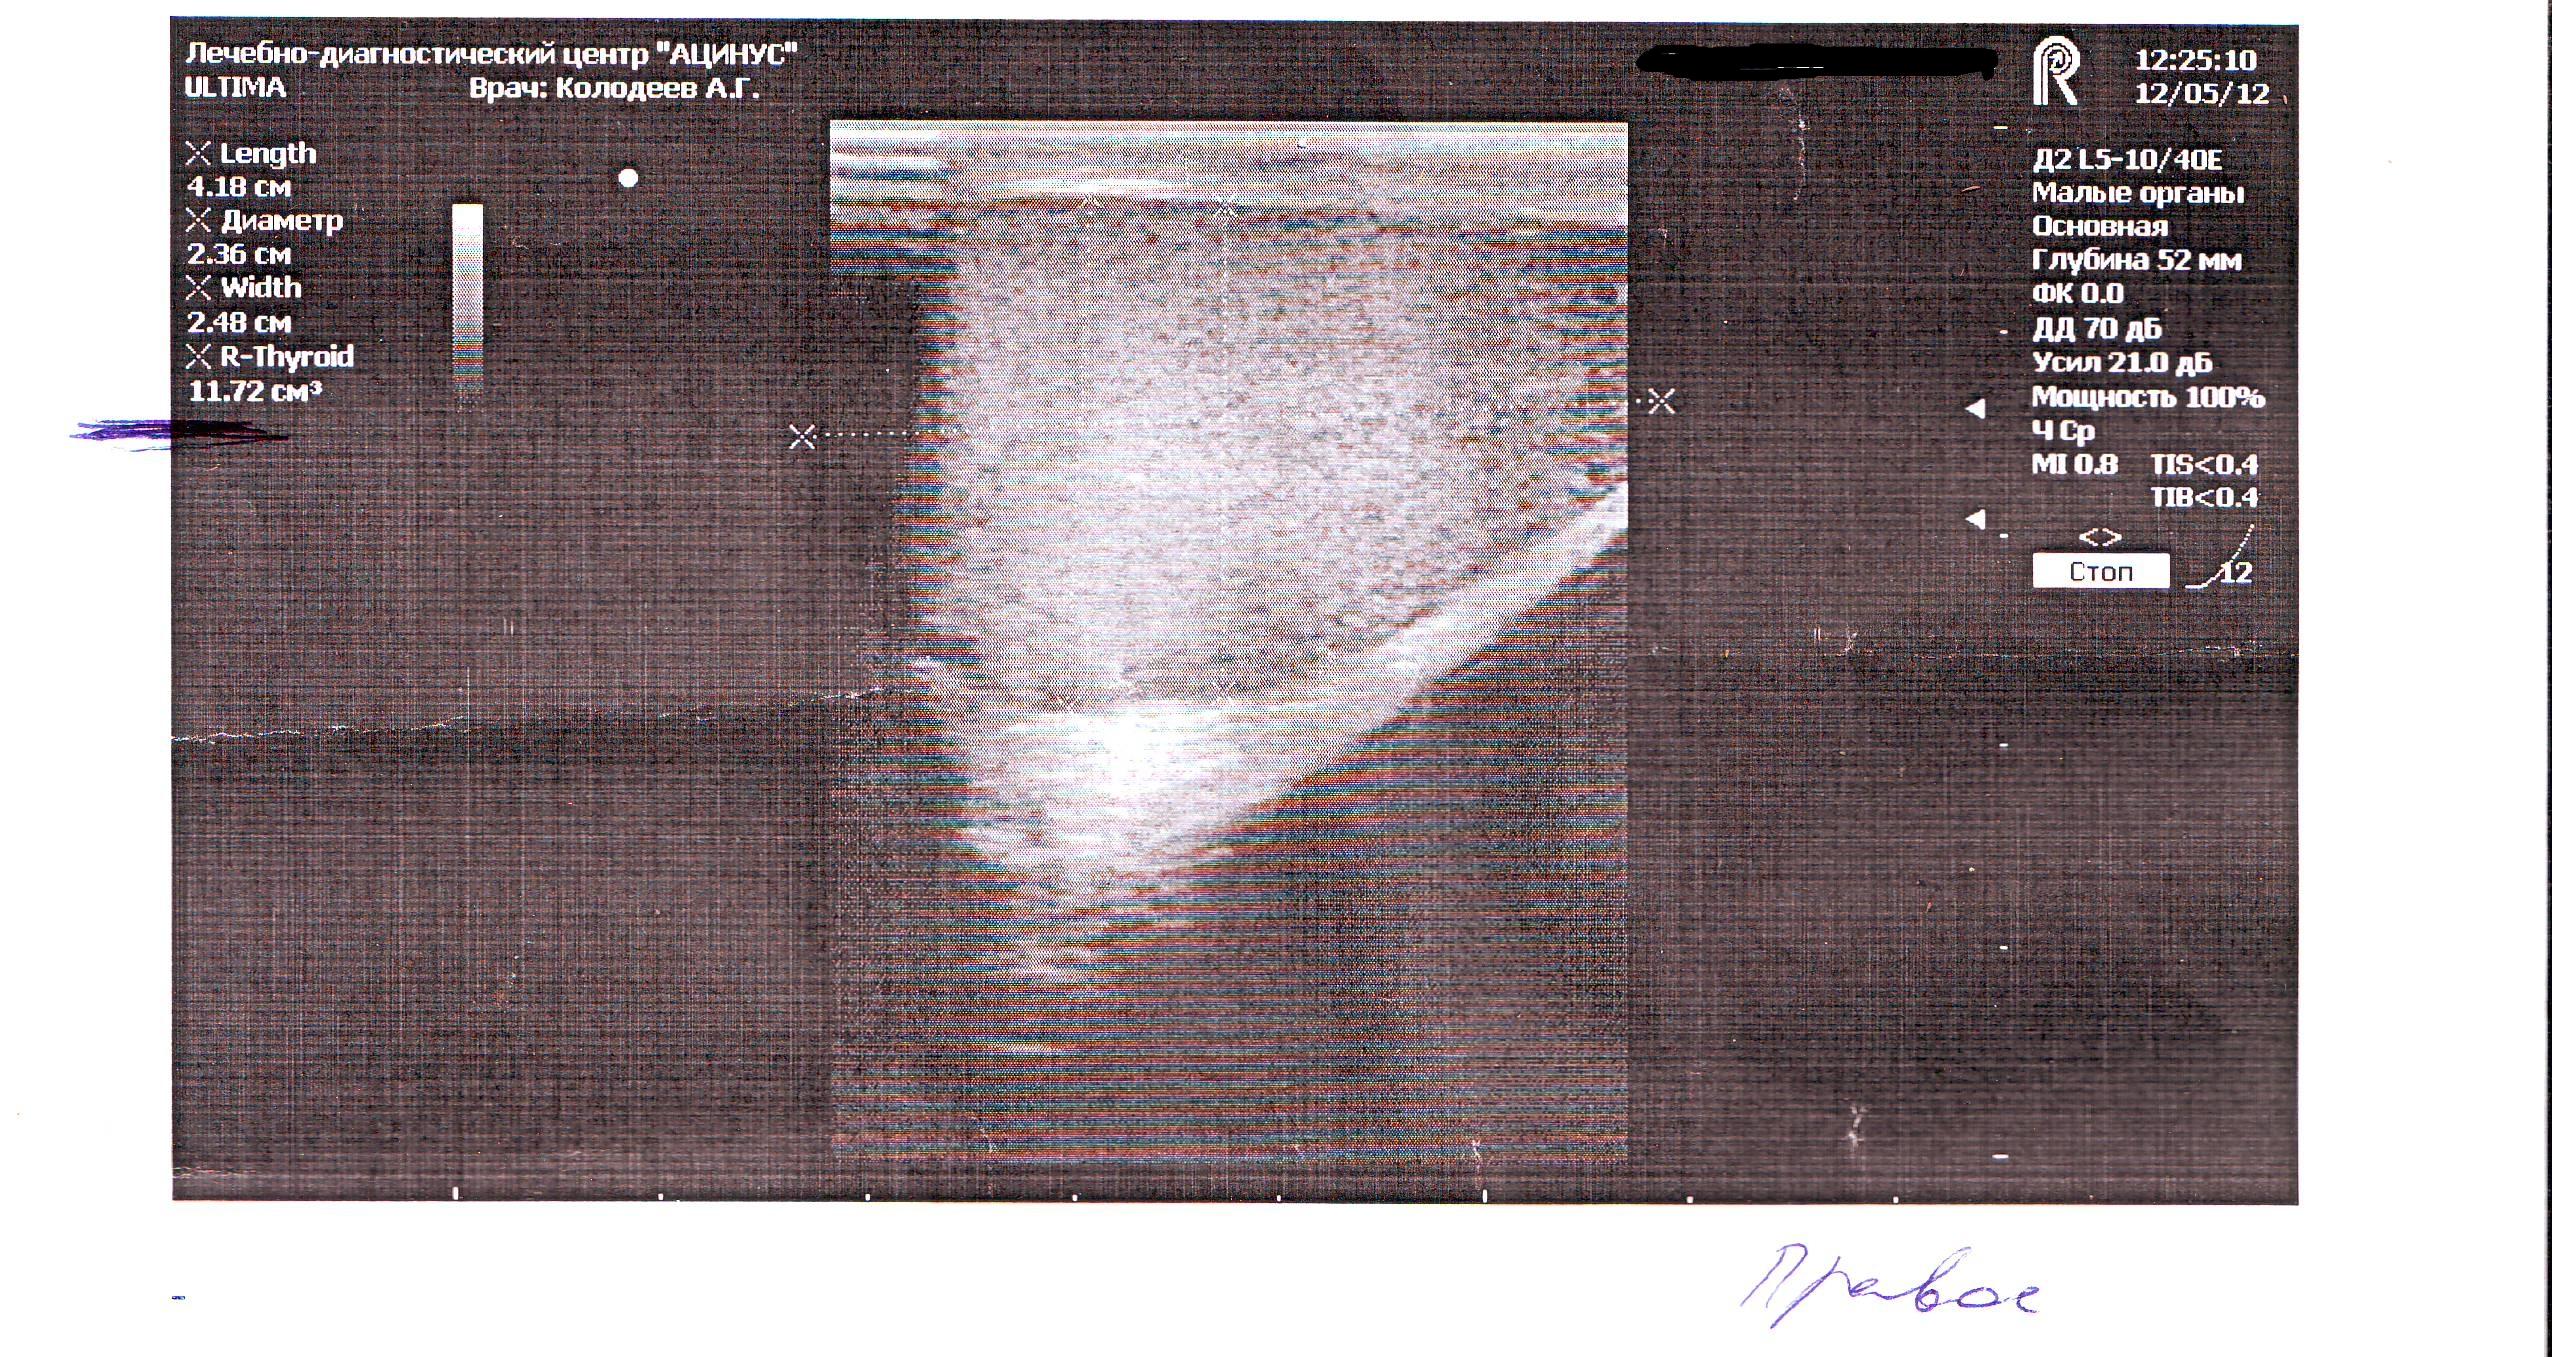

Здравствуйте у меня болели яички особенно левое пошёл к врачу сказал застой простаты, принимал препараты и заметил что яички уменьшились в размерах особенно левое и оно оттягиваеться иногда еще вниз сделал узи как указано в записи всё вроде хорошо так почему не пойму они уменьшились я так понял это атрофия яичек? можно ли восстановить размер?